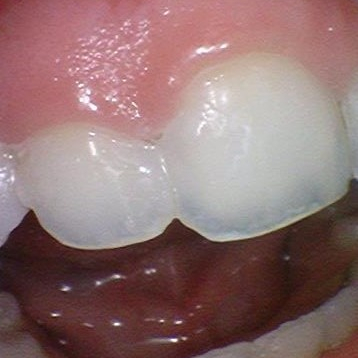

![[을지로/명동 근처 치과] 앞니 레진 치료사례 관련 이미지 2](https://pub-9f2bb3498faf4d1d8714b41df24753e3.r2.dev/content/clinics/archive/rseeanjxfu/naver_blog/yonseiyegam/assets/by_hash/53f27399006ef9c663d823053cca4e675c5621f1bc854b54bf1e94edfd52c304.jpg)

![[을지로/명동 근처 치과] 앞니 레진 치료사례 관련 이미지 3](https://pub-9f2bb3498faf4d1d8714b41df24753e3.r2.dev/content/clinics/archive/rseeanjxfu/naver_blog/yonseiyegam/assets/by_hash/1b87c72e6749b3b7857cd2219bc1f6364e909185d1acadcf3a38cfe55f34c376.jpg)

타치과 3개월된 레진이 떨어져서 치아치료 전과 후